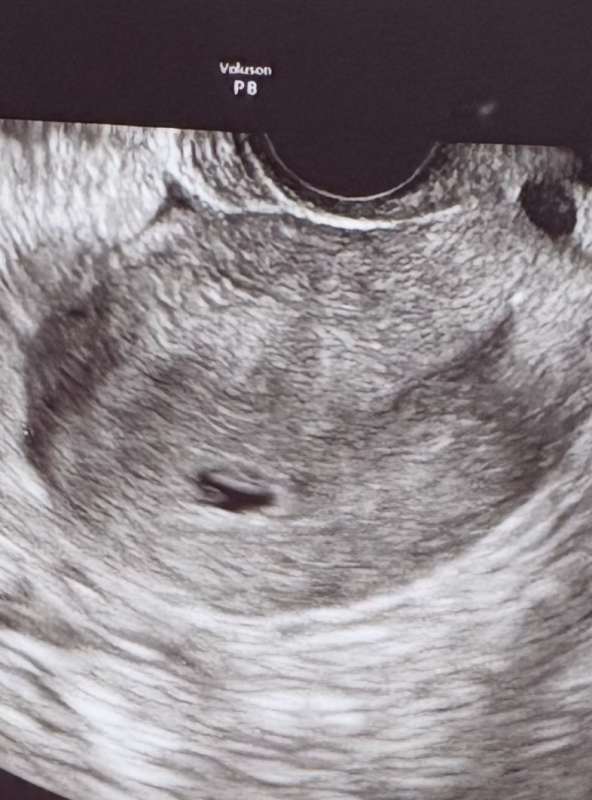

体外受精でBT12に陽性判定(hcg471)、BT23(6w0d)にエコーにて胎嚢と卵黄嚢確認できました。

あわよくば心拍も確認できるかなー?と思っていましたが、胎嚢9.8mmとやや小さめでした。

卵黄嚢あると言われましたが不安なエコー所見になりました。

また、胎嚢の形が楕円で歪な気がするのと

12時の方向に横長に白く映るものはなんでしょうか?

横長に白く映るものは何になるのか、はっきりとしたことはわからないのですが、膜のようなものがあるのかなと思いました。